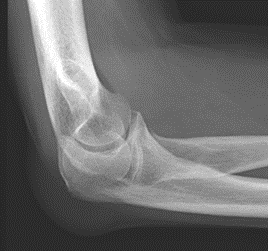

Świadczenie usług medycznych …

Radiogram przedstawia

Ilustracja do pytania 19

A. ciężki uraz miednicy w mechanizmie stycznym.

B. prawidłową miednicę 10-letniego chłopca w ocenie panewki.

C. prawidłową miednicę u osoby starszej w ocenie panewki.

D. złamanie w obrębie szyjki kości udowej z przemieszczeniem linii Shentona.